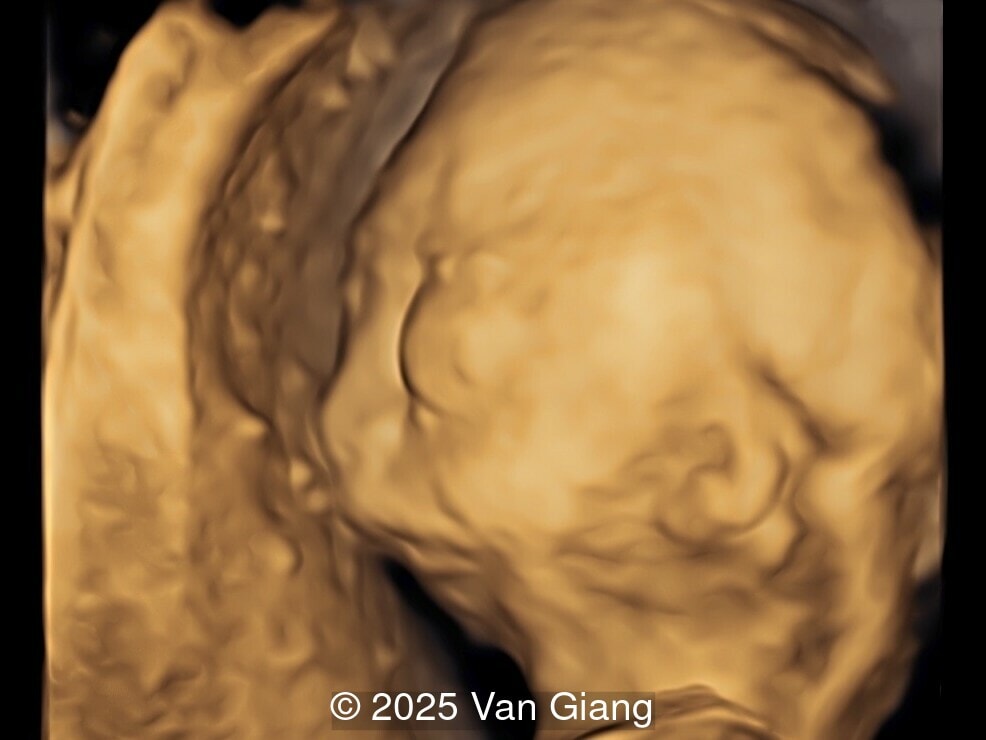

Image 1

Ultrasound revealed severe mandibular and zygomatic hypoplasia, glossoptosis, cleft palate, and micrognathia with an abnormal facial profile. Both upper limbs showed radial ray sequence with abnormal thumbs and shortened forearms. Unilateral clubfoot was also noted. No major cardiac or visceral anomalies were observed. Based on these findings, Nager syndrome was suspected.

fetal profile

Image 1 fetal profile